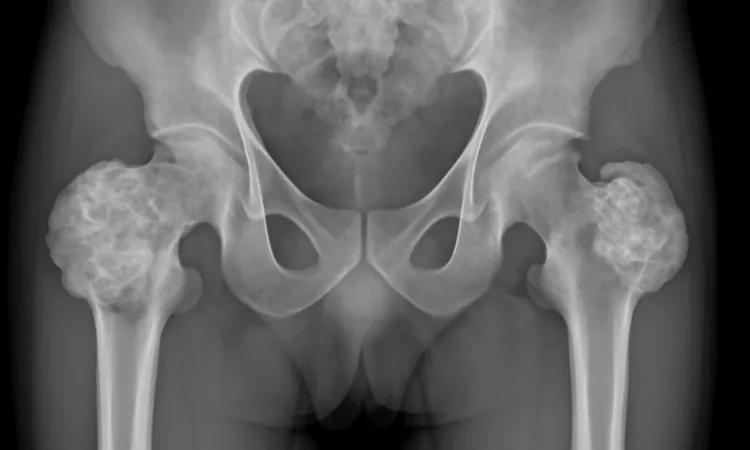

Диагностика новообразований и опухолей тазобедренного сустава является важным этапом в лечении. Для определения характера образования и его стадии проводятся различные исследования. МРТ тазобедренного сустава заняло ключевую позицию в этом процессе благодаря своей высокой информативности и безопасности.

Первым шагом в диагностике обычно становится клинический осмотр пациента. Врач оценивает симптомы, такие как болевые ощущения и ограничения в движении. Затем назначаются дополнительные исследования, чтобы уточнить диагноз. Важными методами являются:

1. Рентгенография – позволяет выявить изменения в костной ткани, однако ограничена в определении мягкотканевых образований.

2. Магнитно-резонансная томография (МРТ) – дает детальное изображение не только костей, но и окружающих мягких тканей, суставной сумки и связок. Это исследование помогает в выявлении как доброкачественных, так и злокачественных опухолей.

3. Компьютерная томография (КТ) – используется для более глубокого анализа костных структур, что может быть полезно в сложных случаях.